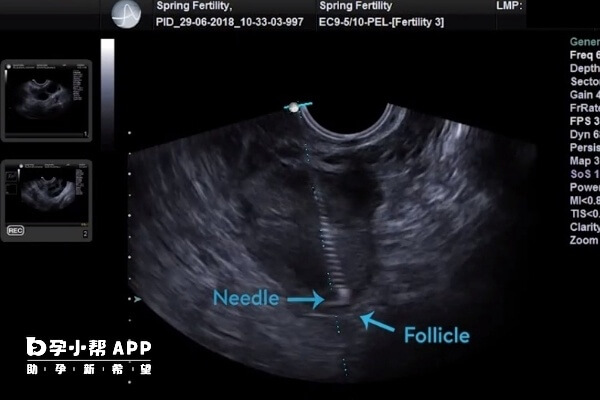

有一些患者由于有大量的腹水,就会出现一些取卵后腹水的症状,患者会感觉明显的腹胀,甚至会有腹部疼痛的情况。这种情况下除了增加饮食营养以外,可以输注白蛋白进行治疗,必要的时候可以行穿刺抽液来减少腹水的量。